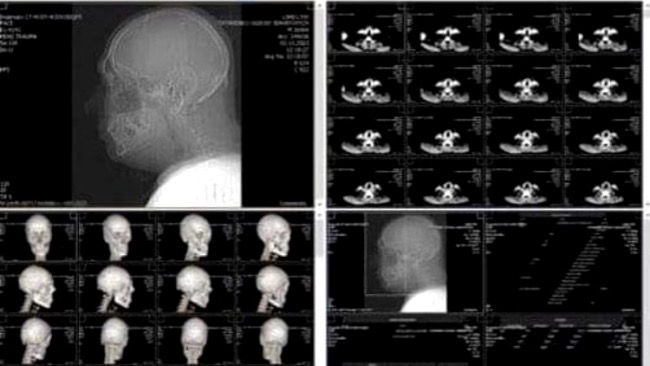

Our friendship flourished in challenging wartime conditions, where we together helped those in need. However, fate brought difficulties to Aleks when, on December 3, 2023, during a Ukrainian military counteroffensive, he participated in the dramatic evacuation of injured soldiers from the front. As a result of an accident, he suffered a complicated jaw fracture.

He cannot eat, speak, or lead a normal life. To enable him to function normally and continue helping people, he needs an operation that costs 3000 euros. Due to the challenging wartime situation, the Ukrainian government does not fund such operations. This means that the temporary solution that was supposed to be in place unfortunately extends due to a lack of funds. Wiring and splints for over a month now cause him immense discomfort.